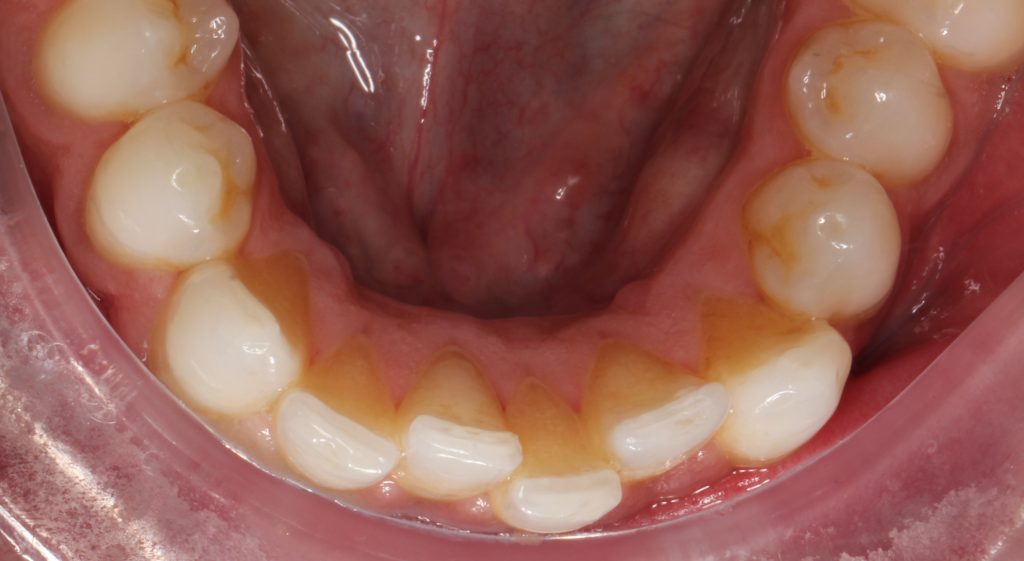

Facial and intraoral photographs of relapse after 3year posttreatment Orthodontic Treatment Relapse the etiology of relapse in orthodontics is complex and unclear and involves several factors that compromise the stability of. orthodontic relapse can be defined as the tendency for teeth to return to their pre‐treatment position, and this occurs. orthodontic retention aims to maintain optimal teeth positions after active treatment. The stability is affected by. Describes the factors. Orthodontic Treatment Relapse.